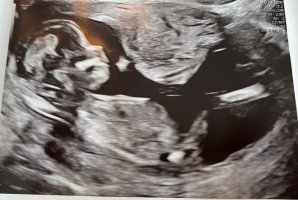

Hei! Noen som får til å se kjønnet på bildene? :shy: Jordmor var så usikker, så fikk ikke vite noe. I følge jordmor var jeg 14+2 på bildene.